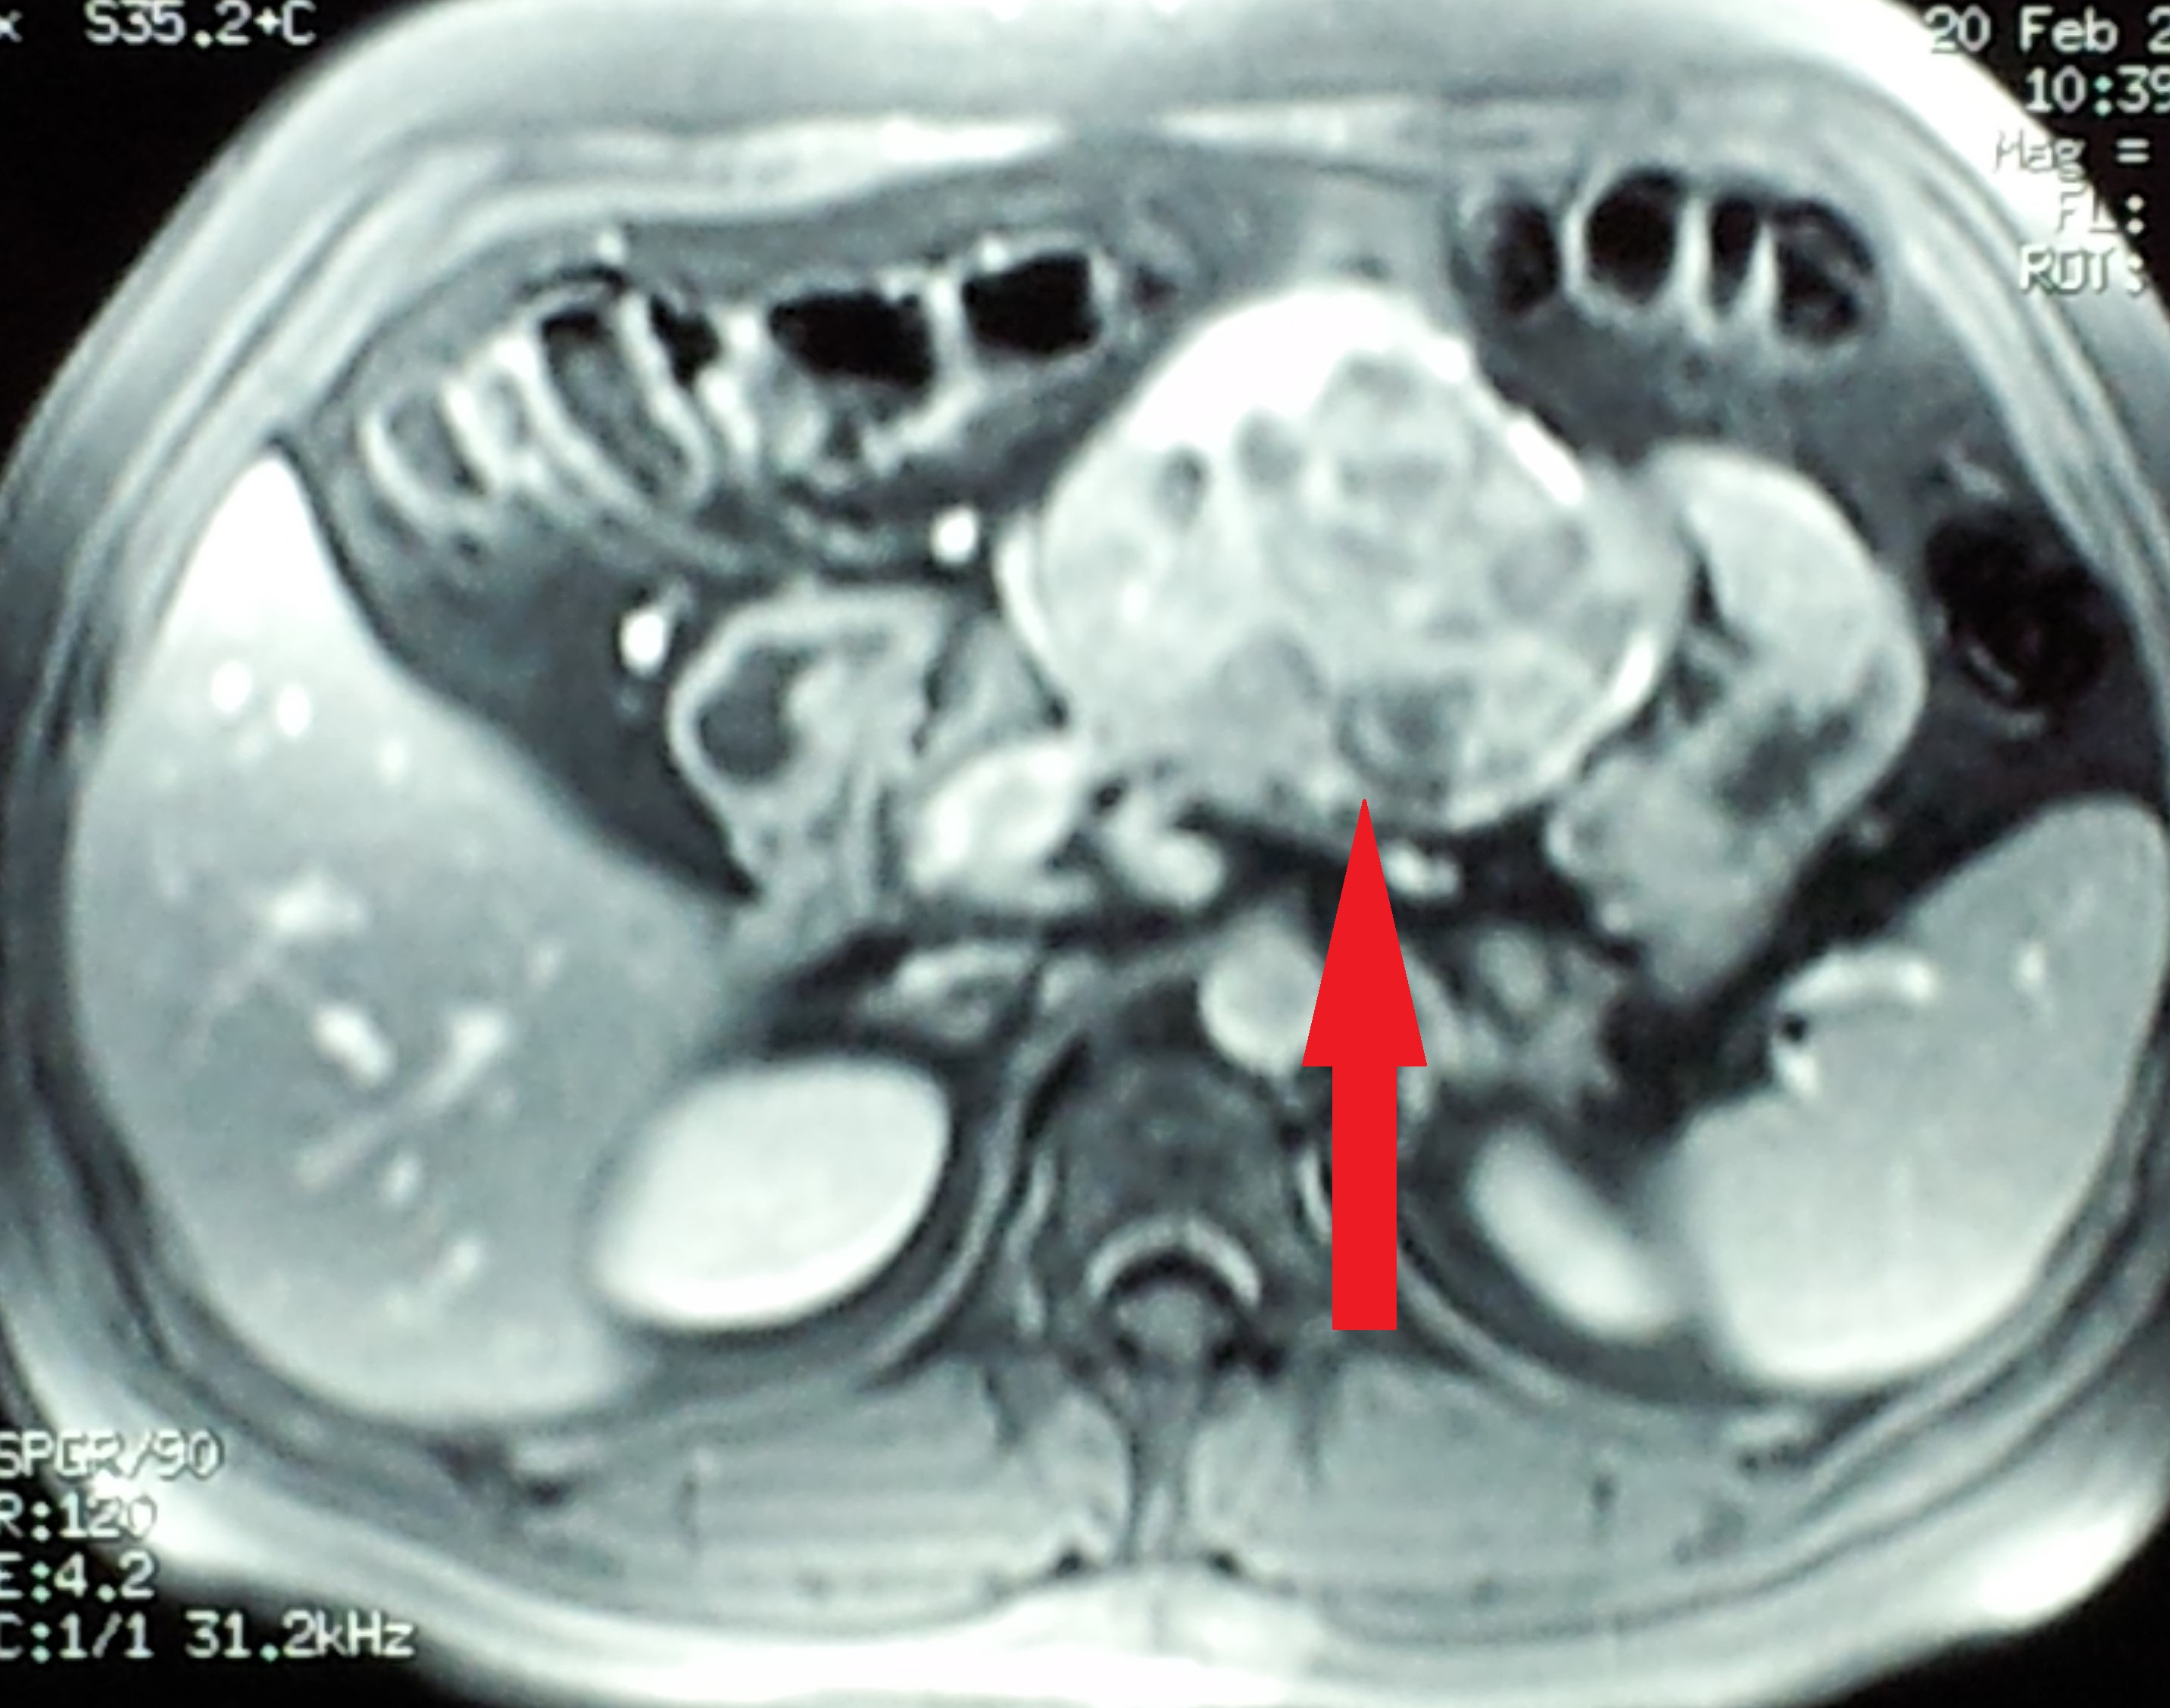

MRI κοιλίας που δείχνει το ευμεγέθες παραγαγγλίωμα στη ρίζα του μεσεντερίου (Ευγενική παραχώρηση Dr. V. Penopoulos)